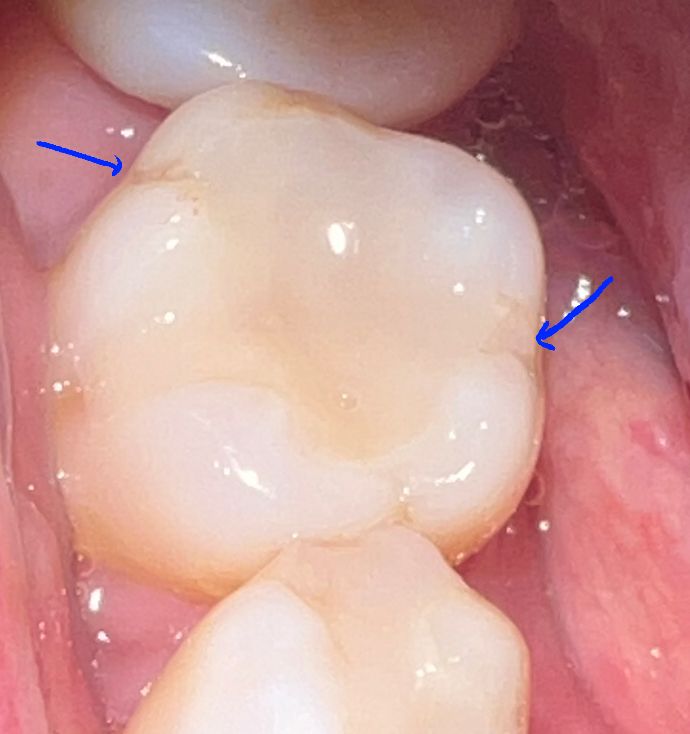

인레이 교체 후 날카로운 부분은 다듬지 않아도 되나요?

치아 갈아낸 부분을 인레이가 완전히 덮지를 못하고 있는 것으로 보이는데요.

화살표 친 부분이 너무 날카로와 보입니다. 부드럽게 연마해야 하는 거 아닌가요?

사진상 특별히 날카로워보이지는 않지만 불편하다면 치과에 말씀하셔서 다듬으면 됩니다.

인레이를 한뒤에 날카로운 부위는 다듬을수 있습니다

불편감이 있다면 치료한 치과에서 다듬어 보세요